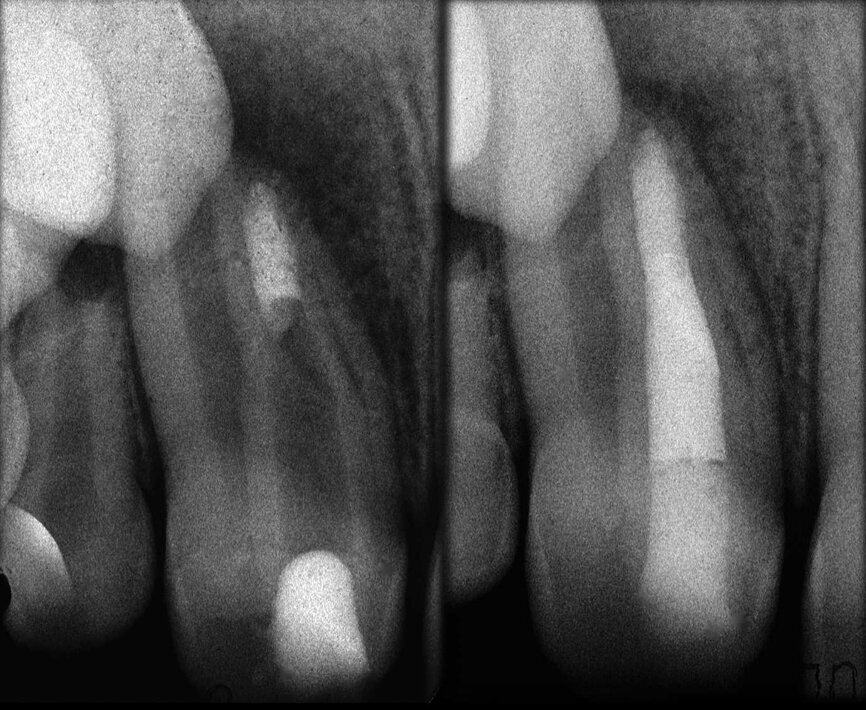

Le cas avec lequel je souhaite commencer mon exposé clinique est un exemple parfait de la difficulté à définir l’origine des symptômes d’un patient, par l’examen d’une simple radiographie intraorale. Non seulement l’examen 2D ne permet pas d’établir avec certitude la présence d’une lésion, mais surtout, il est impossible d’en déterminer la taille, la morphologie et le type. Au contraire, une analyse de l’imagerie 3D offre une image claire de la situation clinique. Chez ce patient, les coupes coronales et sagittales révèlent la présence d’une importante lésion s’étendant de l’apex de la racine mésiale de cette molaire jusqu’à la zone de furcation, tandis que les coupes axiales nous permettent d’analyser précisément l’anatomie endodontique et, en particulier, la forme de la racine mésiale, qui apparaît fusionnée avec la racine palatine. Un panorama complet du cas peut donc guider le processus de décision et orienter le plan de traitement vers une modalité bien précise de traitement (Figs. 1–4).

Dans la prémolaire maxillaire présentée dans les figures 5 et 6, le fistulogramme indique la présence d’une lésion apicale, qui s’étend en direction coronaire jusqu’au tiers moyen de la racine. La décision clinique pourrait donc s’orienter vers un retraitement orthograde ; toutefois, le cliché CBCT nous donne une tout autre vision de la situation que celle de la radiographie, dans la mesure où il montre une lésion irréversible de la dent due à un traitement antérieur, et la nécessité de l’extraire.

Il en va tout autrement pour la prémolaire mandibulaire présentée dans les figures 7 à 9 où, malgré l’absence de signes radiologiques de lésion et le traitement endodontique visiblement correct réalisé par un autre confrère, le patient se plaint d’une douleur persistante, qui est à la fois spontanée et déclenchée par un test de percussion de la dent. Dans ce cas, l’excellent traitement endocanalaire réalisé précédemment semble indiquer le besoin de recourir à une approche endodontique chirurgicale, susceptible de garantir un taux de réussite plus élevé que celui d’un simple retraitement. Étant donné le doute sur le diagnostic, nous avons décidé de réaliser un examen 3D et celui-ci révèle une lésion endodontique causée par un canal lingual resté sans traitement. Grâce à ce diagnostic exact, il devient possible d’envisager une intervention ciblée sur la pulpe restante, et de réaliser un traitement efficace du canal non traité.